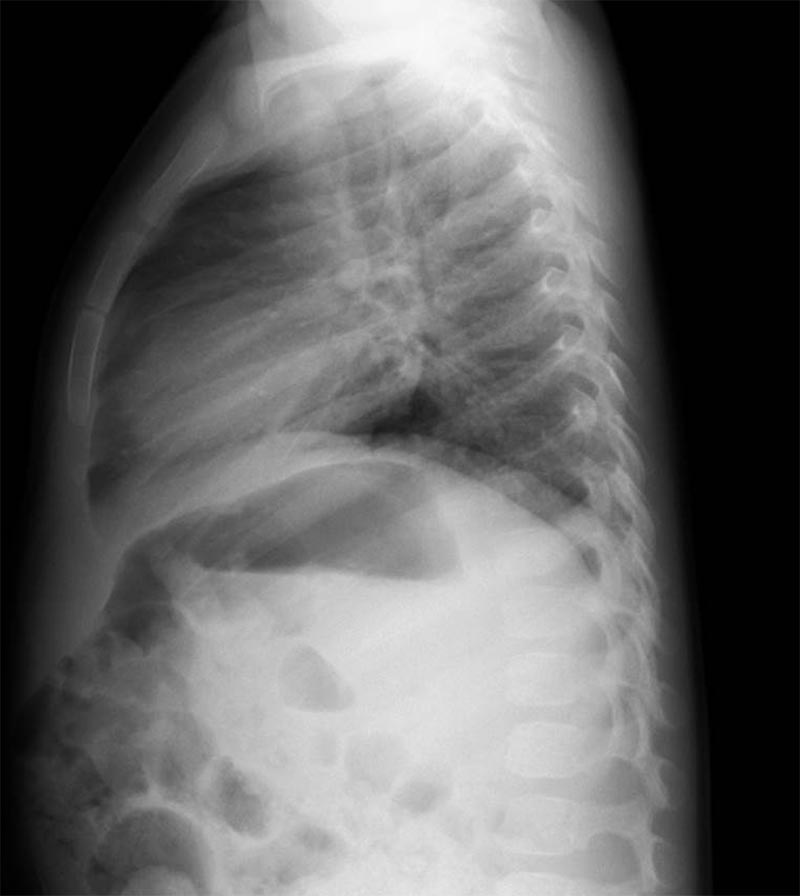

10-month-old male infant presents to the ED by EMS with vomiting and altered mental status (AMS). Infant arrives to the ED awake but poorly interactive. Ultimately, the infant will be diagnosed with intussusception and hypovolemic shock based on the history, physical exam and ultrasound findings. Learners are expected to establish a differential diagnosis of AMS appropriate for an infant, demonstrate appropriate resuscitative interventions, and use appropriate imaging and labs to help identify the cause of AMS.